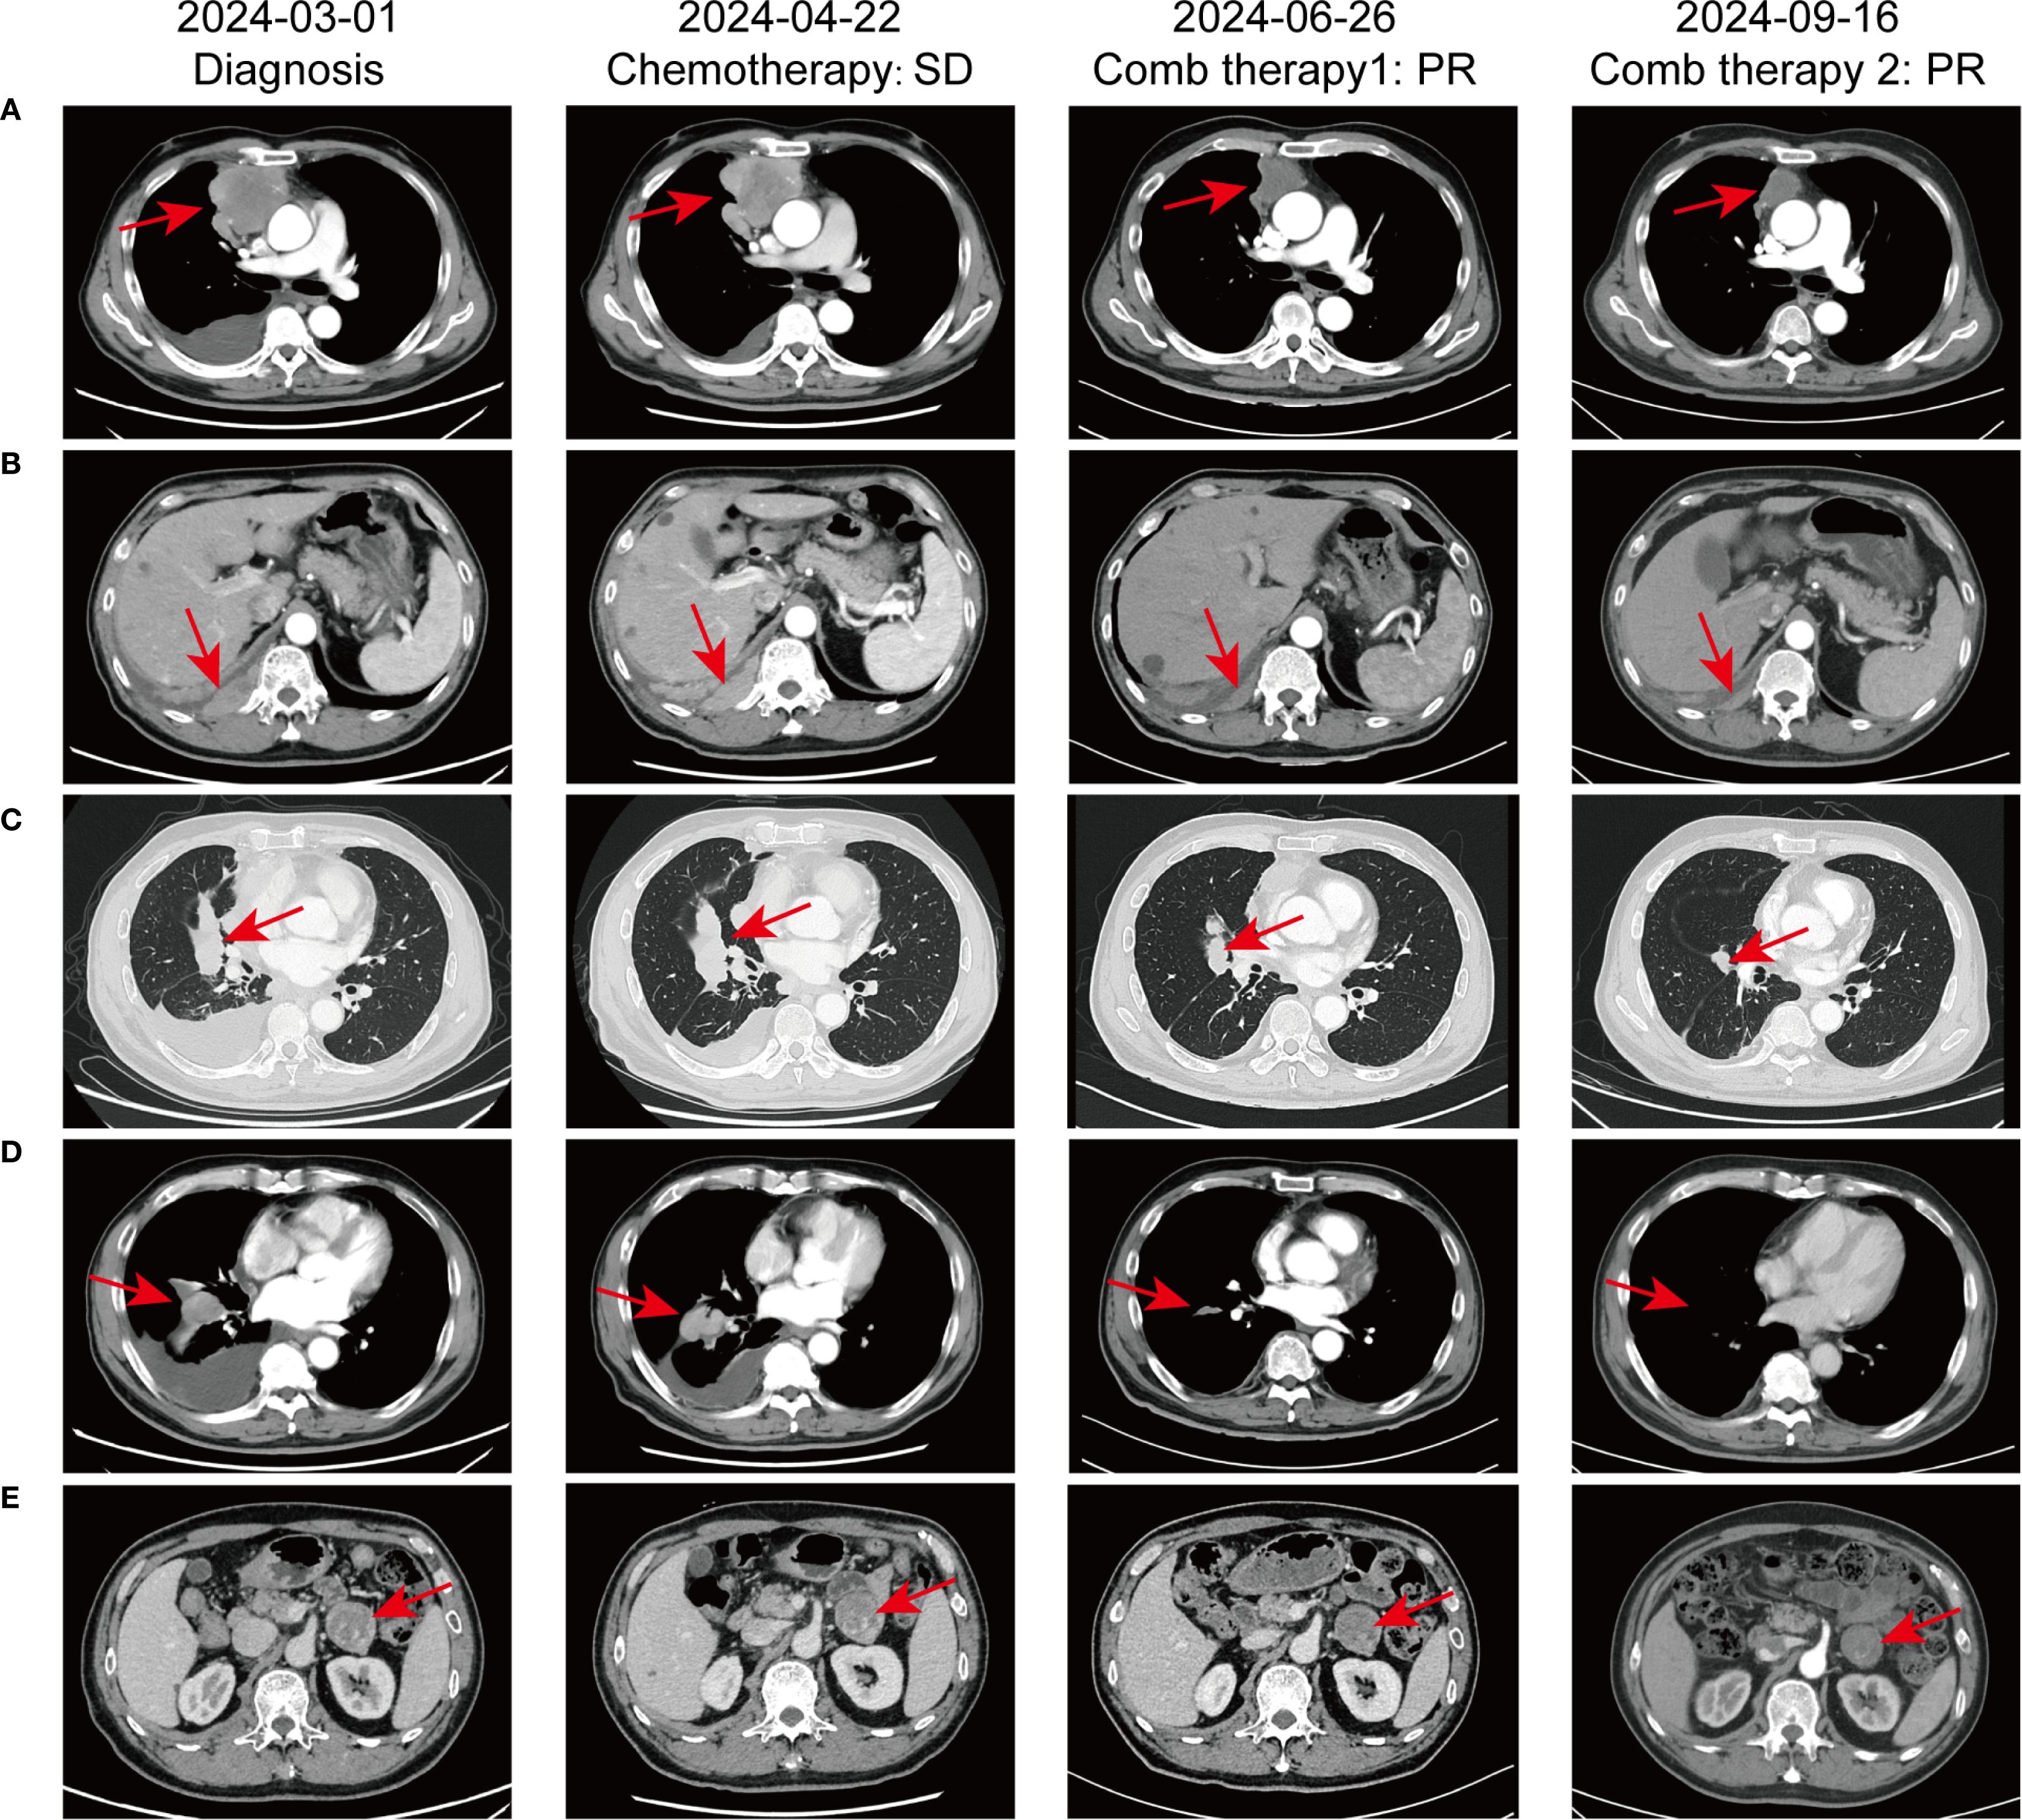

In February 2024, a 60-year-old male patient presented with a 1-month history of a dry cough and fatigue without an apparent cause, which prompted a visit to a local hospital. A chest computed tomography (CT) scan revealed a right lung mass. For further evaluation and treatment, the patient was admitted to our oncology department on March 1, 2024. Enhanced chest and whole-abdomen CT scan showed a space-occupying lesion in the right middle lobe (RML) of the lung, multiple solid nodules in both lungs, multiple soft tissue density shadows in the right pleura, an inhomogeneous enhancing lesion in the left adrenal gland, a mass-like soft tissue density shadow in the anterior mediastinum, and multiple enlarged lymph nodes in the mediastinum and right hilum (Figure 1). On March 5, 2024, CT-guided right lung mass biopsy indicated invasive carcinoma. IHC showed CK5/6(+), P40(+), P63(+), TTF-1(-), Napsin A(-), CD5(+), and CD117(+), with a Ki-67 ~35% (Figure 2). Multidisciplinary diagnosis confirmed advanced thymic squamous cell carcinoma, with metastasis to lung, right pleura, left adrenal gland, and mediastinal and right hilar lymph nodes (cT3N2M1b, Stage IVB). Biomarker and NGS analysis revealed PD-L1 negativity (TPS<1%, details in Supplementary Table 1). Tumor markers abnormally elevated: CA125–274 ng/mL (ref: 0-24.00), CYFRA211 26.89 ng/mL (ref: 0-3.3) (Figure 3).

Figure 1. Comparative chest CT scans illustrating the progression of pulmonary lesions throughout the patient’s treatment course. (A) Irregular mass-like soft tissue shadow in the anterior superior mediastinum; (B) Mass-like soft tissue shadow in the right pleura; (C) Mass in the right middle lobe of the lung; (D) Multiple lymph node metastases in the mediastinum and right hilar lymph nodes; (E) Metastasis to the left adrenal gland.

For unresectable disease, the patient underwent three cycles of first-line chemotherapy from March 7 to April 20, 2024: PM-PTX 360 mg D1 q3w + carboplatin 450 mg D1 q3w. A follow-up chest CT on April 22 showed largely unchanged lesions after treatment, resulting in an efficacy evaluation of stable disease (SD) (Figure 1). CA125 and CYFRA211 remained elevated (Figure 3). The patient experienced tolerable chemotherapy side effects, including decreased appetite and slight weight loss.

To reduce tumor burden, we evaluated the feasibility of immunotherapy and oral anti-angiogenic agents. Based on the REMORA study, lenvatinib has been shown to provide survival benefits for thymic carcinoma patients who have undergone first-line platinum-based chemotherapy (7). Consequently, from May 11 to June 25, 2024, the patient received three cycles of PM-PTX 360 mg D1 q3w + carboplatin 450 mg D1 q3w + tislelizumab 200 mg D1 q3w + lenvatinib 8 mg qd. CT on June 26, 2024, showed reduction of both primary and metastatic lesions. The efficacy evaluation indicated a partial response (PR), confirming the initial effectiveness of the added immunotherapy. CA125 significantly decreased to 53.6 ng/mL, CYFRA211 to 9.74 ng/mL; WBC level remained within the normal range (Figure 3). Throughout the treatment period, the patient maintained a positive mental state, experienced reduced toxic side effects from the medications, and no adverse reactions to the immunotherapy were observed.

Given the cumulative toxicity resulting from the long-term use of chemotherapeutic drugs, carboplatin was discontinued. From July 27 to November 9, 2024, the patient underwent five cycles of PM-PTX 360mg D1 q3w + tislelizumab 200mg D1 q3w + lenvatinib 8mg qd. After three cycles of combination therapy, CT on September 16 revealed further shrinkage of the primary and metastatic lesions compared to June 25, with minor chronic inflammation observed in the right lung and the lower lobe of the left lung. The efficacy was evaluated as PR, confirming that the combination therapy has effectively controlled the patient’s condition. CA125 and CYFRA211 neared normal, and WBC remains within the normal range (Figure 3). During the five cycles of combined treatment, the patient demonstrated an improved mental state, further alleviation of clinical symptoms, and steady weight gain. The toxic side effects of anti-tumor treatments, particularly immunotherapy, can significantly impact the patient’s quality of life and adherence to treatment (8). However, over total eight immunotherapy cycles administered in two phases, the patient experienced no grade ≥3 irAEs. Only grade 1–2 toxicities were observed, including forearm erythema, abdominal discomfort, and mildly elevated transaminases (Supplementary Table 2). Tumor condition improved significantly with preserved quality of life. Treatment schedule is illustrated in Figure 4.